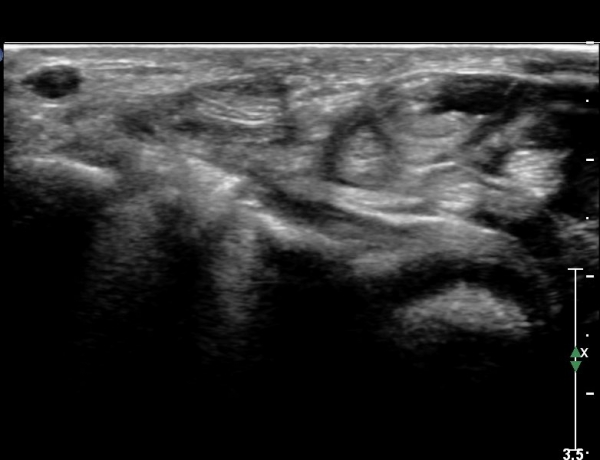

ŽÃËÀÚ¸¦ Á¶±Ý ¸»´ÜÀ¸·Î À̵¿ÇÏ´Ï FPL Å©±â°¡ ±Þ°ÝÈ÷ °¨¼ÒÇÔ. FCR,  FDP ÁÖº¯ ¹Ì¼¼ÇÑ ¼ö¾×Àú·ù °üÂûµÊ(»çÁø4, 5)

ŽÃËÀÚ¸¦ Á¶±Ý ´õ ¸»´ÜÀ¸·Î À̵¿ÇÏ´Ï FCR¿Í FDP »çÀÌ¿¡¼­ Àú¿¡ÄÚ »óÅÂÀÇ FPL °¡ °üÂûµÇ°í °íÁ¤¹°¿¡ ÀÇÇÑ

¾Ð¹ÚÀÌ °üÂûµÊ(»çÁø 6, 7)